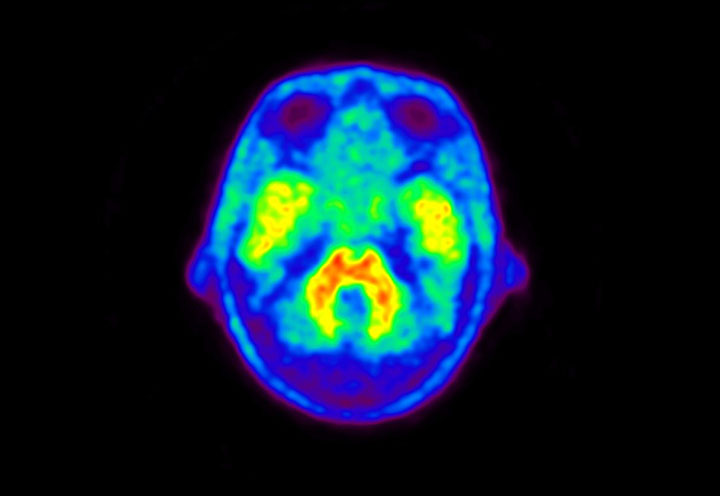

Head / Case5 : Amyloid

Courtesy : Kindai University Hospital

- Imaging protocol

- Injected dose: 4.27 MBq/kg, 18F-Flutemetamol

- Uptake time: 99 minutes

- Scan time: 20 minutes